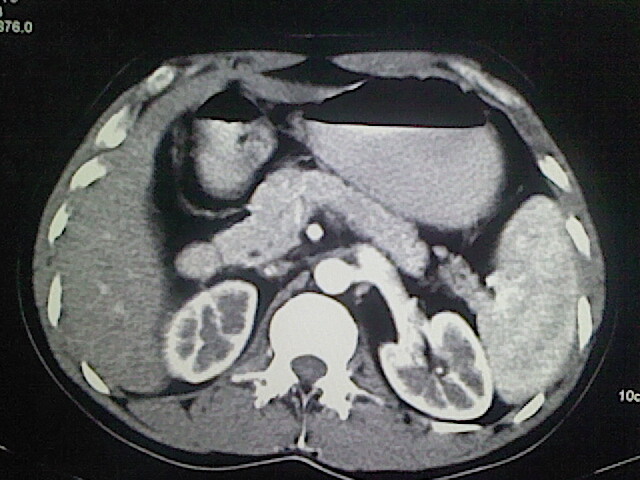

以下是引用卜一在2009-3-14 9:49:00的发言:[br]胆囊萎缩,胆囊壁不规则增厚,内部结构模糊,增强明显强化。另:肝左叶外侧段肝囊肿。支持:慢性胆囊炎!高度可疑:胆囊癌!

以下是引用余辉在2009-3-14 8:48:00的发言:[br]1)慢性胆囊炎。2)肝左叶外侧段肝囊肿。3)脂肪肝。[br]支持,胆囊萎缩,密度增高,不知b超具体有何提示,钙胆汁?结石?

以下是引用jiangjing在2009-3-14 10:18:00的发言:[br]1)慢性胆囊炎。2)肝左叶外侧段肝囊肿。3)脂肪肝。4.】建议行肝功能检查